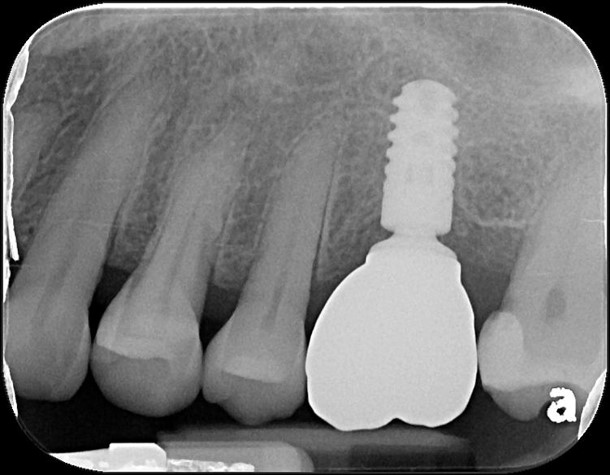

植牙後,角度良好

6個月後植牙骨整合